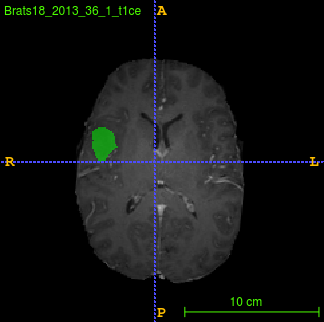

Segmentation of brain tumor from magnetic resonance imaging (MRI) is a vital process to improve diagnosis, treatment planning and to study the difference between subjects with tumor and healthy subjects. In this paper, we exploit a convolutional neural network (CNN) with hypercolumn technique to segment tumor from healthy brain tissue. Hypercolumn is the concatenation of a set of vectors which form by extracting convolutional features from multiple layers. Proposed model integrates batch normalization (BN) approach with hypercolumn. BN layers help to alleviate the internal covariate shift during stochastic gradient descent (SGD) training by zero-mean and unit variance of each mini-batch. Survival Prediction is done by first extracting features(Geometric, Fractal, and Histogram) from the segmented brain tumor data. Then, the number of days of overall survival is predicted by implementing regression on the extracted features using an artificial neural network (ANN). Our model achieves a mean dice score of 89.78%, 82.53% and 76.54% for the whole tumor, tumor core and enhancing tumor respectively in segmentation task and 67.90% in overall survival prediction task with the validation set of BraTS 2018 challenge. It obtains a mean dice accuracy of 87.315%, 77.04% and 70.22% for the whole tumor, tumor core and enhancing tumor respectively in the segmentation task and a 46.80% in overall survival prediction task in the BraTS 2018 test data set.